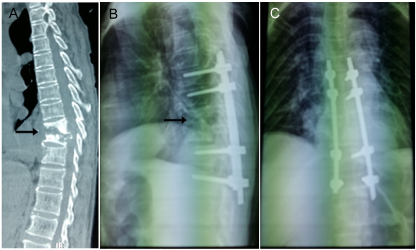

Figure 2. CT images of thoracic spine before and after surgery. (A). A representative of destructed lower thoracic spine (arrow) is indicated in a preoperative CT image; (B). The location of damaged spine is shown in a preoperative MRI photo; (C, D) X-ray images show back and lateral positions of pedicle screws after operation.